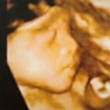

四维照姗姗来迟,26周!

妈妈的乖孩子三次才给个脸蛋。

换个角度

这张好清晰哟,好几个月呀,好像月份很小呀

回复 饭盆 :26周了啊,孩子小些

六个半月啦!五个半月去了说看太小看不清

超说是女孩儿!祝你的宝宝健康可爱!

佳乐今天亲戚们看了你的照片,姥姥阿姨说你像爸爸,其他说你像妈妈,男孩脸。不管男孩女孩,妈妈一样爱你!呵呵。

24+5.双顶径61mm.头围226㎜.腹围201㎜.股骨47㎜.肱骨43㎜胎心140/分。羊水深度51㎜。胎儿体重781g

照片是26W补拍的